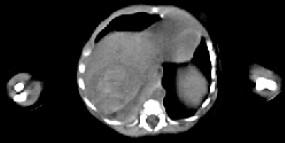

男,5天,上腹部膨隆,CT所见如图,最可能的诊断是 ( )A、肝脓肿B、肝转移瘤C、肝母细胞瘤D、肝血管瘤E、原发性肝癌

问题 男,5天,上腹部膨隆,CT所见如图,最可能的诊断是 ( )

选项 A、肝脓肿 B、肝转移瘤 C、肝母细胞瘤 D、肝血管瘤 E、原发性肝癌

答案 C